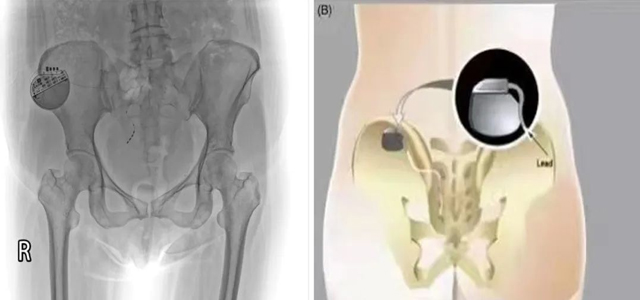

为缓解会阴及盆底疼痛给患者带来的不适感,翟春宝主任及其团队经科室讨论后决定为该患者进行骶神经调控术,并与患者及家属耐心沟通。根据综合评估,择期局麻下行一期骶神经调控器置入术。依据患者肛周感受调节控制器相关数值。

术后3月,患者自觉肛周坠胀明显减轻(自述好转70%以上),大小便控制能力较术前明显改善。患者及家属对一期调控效果非常满意,完善相关检查后行骶神经调节器植入(二期)。

骶神经调控:是指利用介入手段将一种短脉冲的刺激电流连续施加于特定的骶神经,以此剥夺神经细胞本身的电生理特性、以便人为地激活兴奋或抑制神经通路、干扰异常的骶神经反射弧,进而影响由调节盆底等骶神经支配的效应器官的行为,起到“神经调控”的作用。